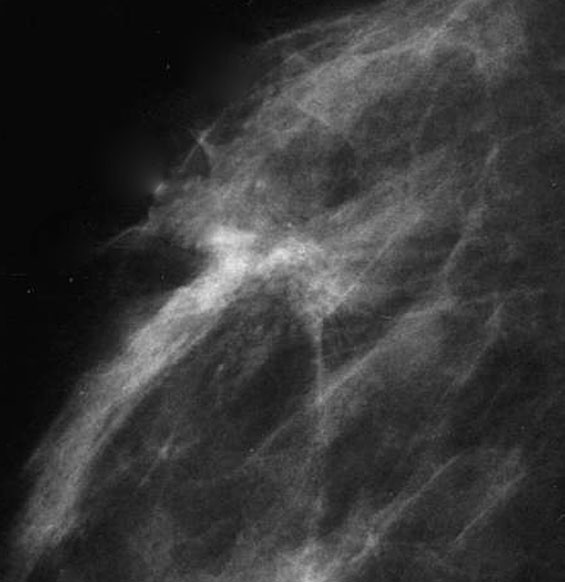

Radiology description

- Ultrasound (Radiographics 2009;29:165)

- Hypoechoic mass with spiculated or ill defined margins and posterior acoustic shadowing

- Mammography (Radiographics 2009;29:165)

- Does not consistently present as a mass (44% - 65%)

- Less commonly manifests as architectural distortion

- Microcalcification infrequent

- Magnetic resonance imaging findings similar (Radiographics 2009;29:165)

- Can aid in identifying multifocal or residual disease

- Preoperative breast MRI may improve surgical planning (Breast J 2016;22:143)

Radiology images